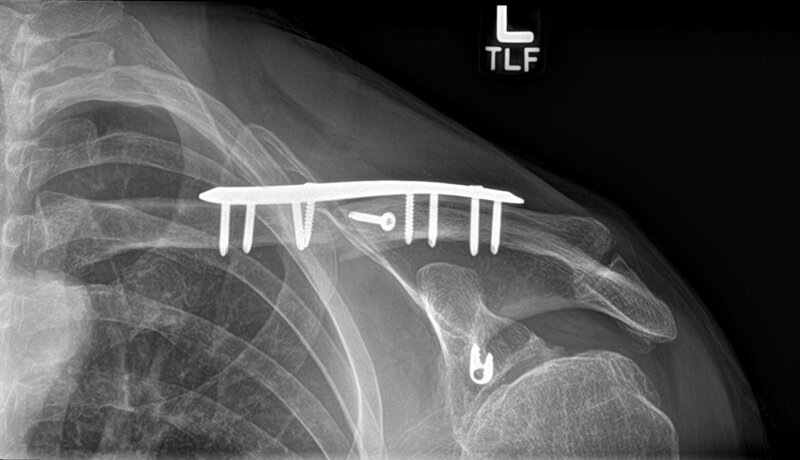

X-ray from this morning:

X-ray from this morning: